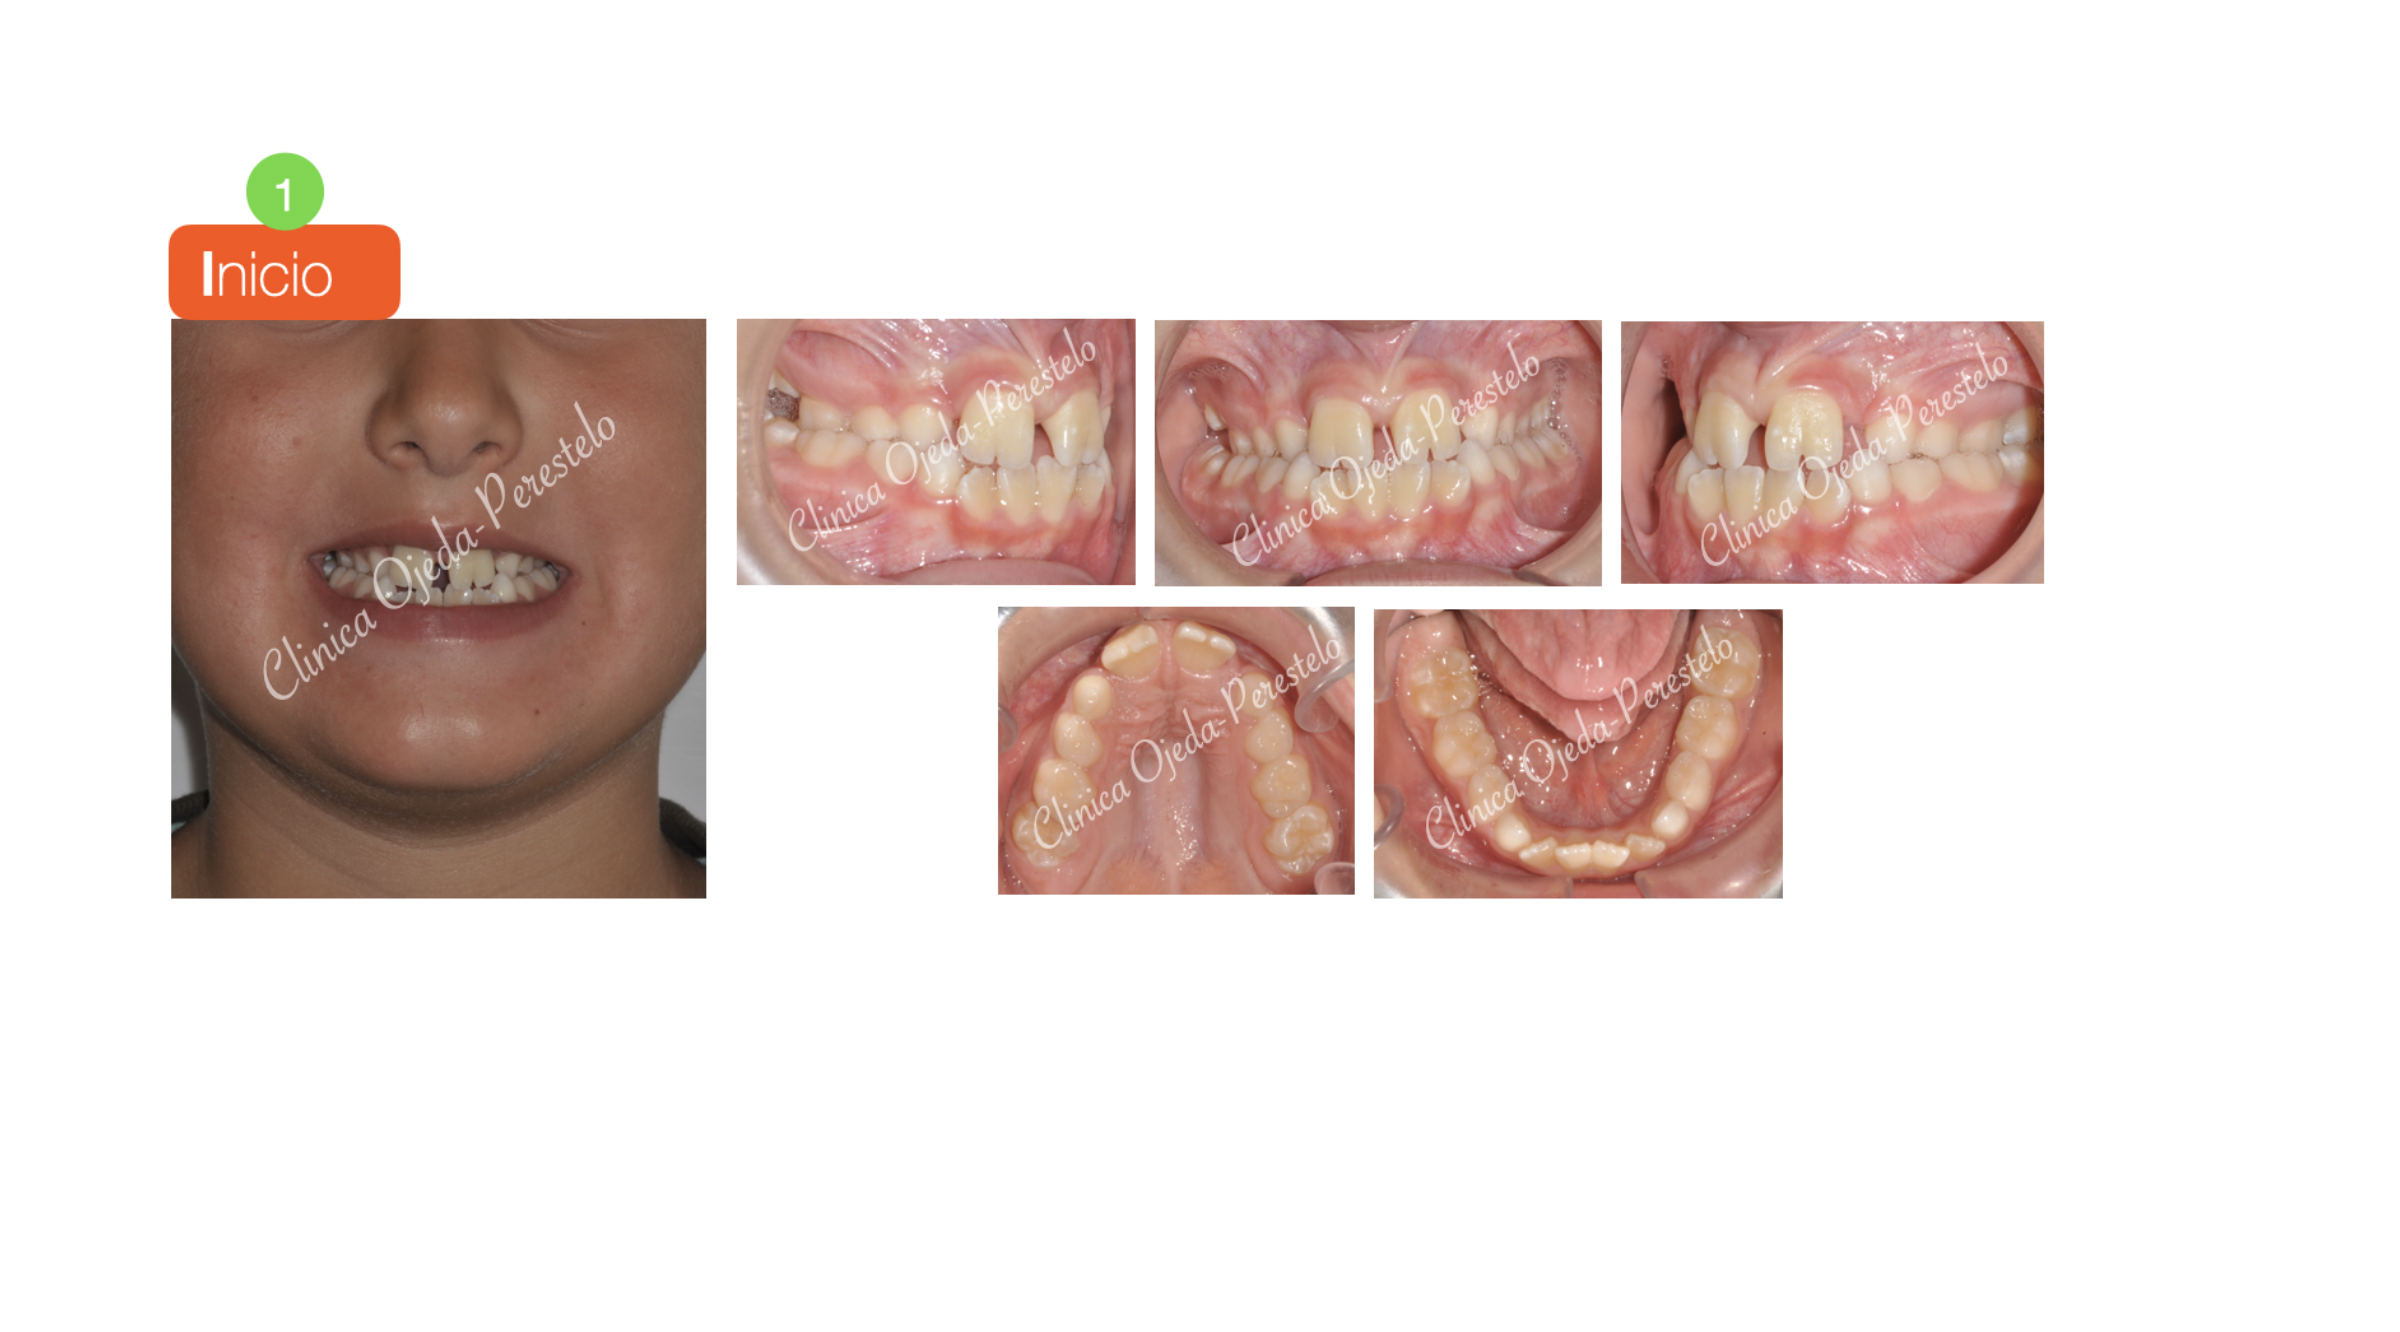

Mordida Cruzada Bilateral

Presentamos a este niño respirador bucal y roncador con Mordida cruzada Bilateral. Decidimos colocarle un Disyuntor Dentosoportado con ganchos para Máscara Facial. Una vez terminada la fase Ortopédica (4 Meses ),comenzamos con la alineación y nivelación de los 4 incisivos con brackets superiores e inferiores (2x4 ). Quisiéramos destacar la mejoría del paciente en la función respiratoria, deglutoria y masticatoria. Sus ronquidos han desaparecido y se ha conseguido una gran amplitud en la sonrisa.